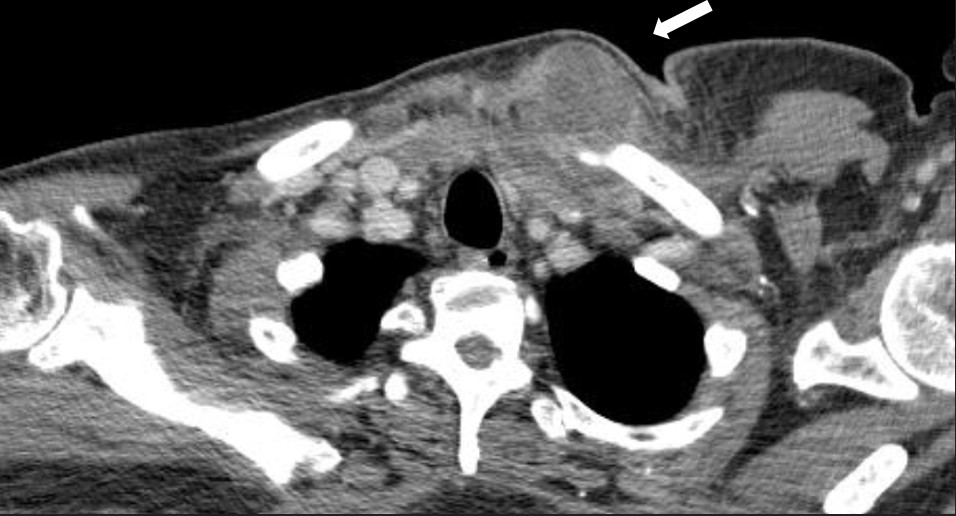

Imaging and laboratory tests indicated an infectious process in the anterior mediastinum, initially interpreted as cellulitis, which progressed to a sternoclavicular abscess. A chest CT scan revealed fat stranding in the mediastinum, narrowing of the right sternoclavicular joint space, heterogeneous attenuation of the muscle planes, and small cystic collections with abscess formation (Fig. 1).

Figure 1. Computed axial tomography. Diffuse bone edema with soft tissue edema also characteristic of osteomyelitis.